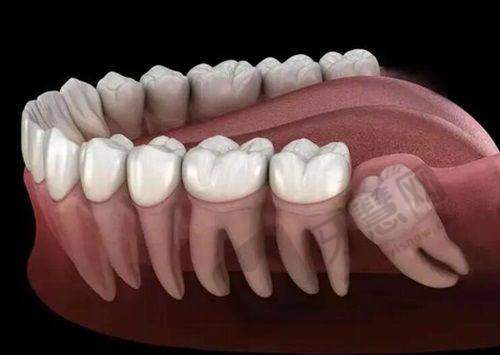

榆林中诺口腔医院是正规私立口腔医疗机构,由榆林市榆阳区行政审批服务局批准成立,登记号为MA70H784561080215D2152 。它区别于“诊所”“门诊部”等级别的口腔机构,具备医院级别的资质,院内口腔设备和医生团队都特别不错,诊疗技术也佳。医院口碑挺好的,作为榆林当地规模较大、人气较高的口腔医院,备受患者信赖。牙友反馈医生技术好,开设项目齐全,收费价格不贵,看牙特别划算。比如有的牙友洗牙不出血,补牙没有异物感;有的牙友种牙后使用起来和真牙没什么两样。在种植牙方面,技术良好,有独特的数字化诊疗技术,能解决各类缺牙问题,还能为长期缺牙造成牙槽骨薄或三高体质的老人制定合适的种植方案。“立得用”种植技术可以在拔牙同期植入种植体,防止牙槽吸收萎缩和病变,还能立刻镶上过渡义齿,缩短疗程,降低费用,而且不受年龄限制。价格方面,韩系奥齿泰种植牙3980元起,美国皓圣种植牙6930元起等。

中诺口腔医院是私立连锁牙科机构,总部位于北京,在多个城市设有分院。部分分院如北京中诺口腔医院拥有正规医院资质,这些资质证明了其在医疗技术、设备设施、服务质量等方面的实力,也为其在业界树立了良好的口碑。在种植牙领域,它拥有显著的技术实力和丰富的临床经验。有由多位口腔医师组成的医疗团队,医生技术娴熟,注重与患者沟通,能制定个性化的种植牙方案。引入立得用种植牙技术,通过3D智能化导板种植系统,实现了精细化定位、即刻种植和即刻负重,缩短了手术时间,减少了患者痛苦,提高了种植牙成功概率和长期稳定性。还配备了完善的口腔诊疗设备,如3D口腔CT、种植机等,提高了诊疗效率和明确性。凭借优质的服务、可靠的技术和显著的疗效,赢得了广大患者的信赖和好评。比如张女士种牙后觉得服务态度好,术后护理和复查特别贴心;李先生种牙过程顺利,术后修复快,种植牙结果特别自然。